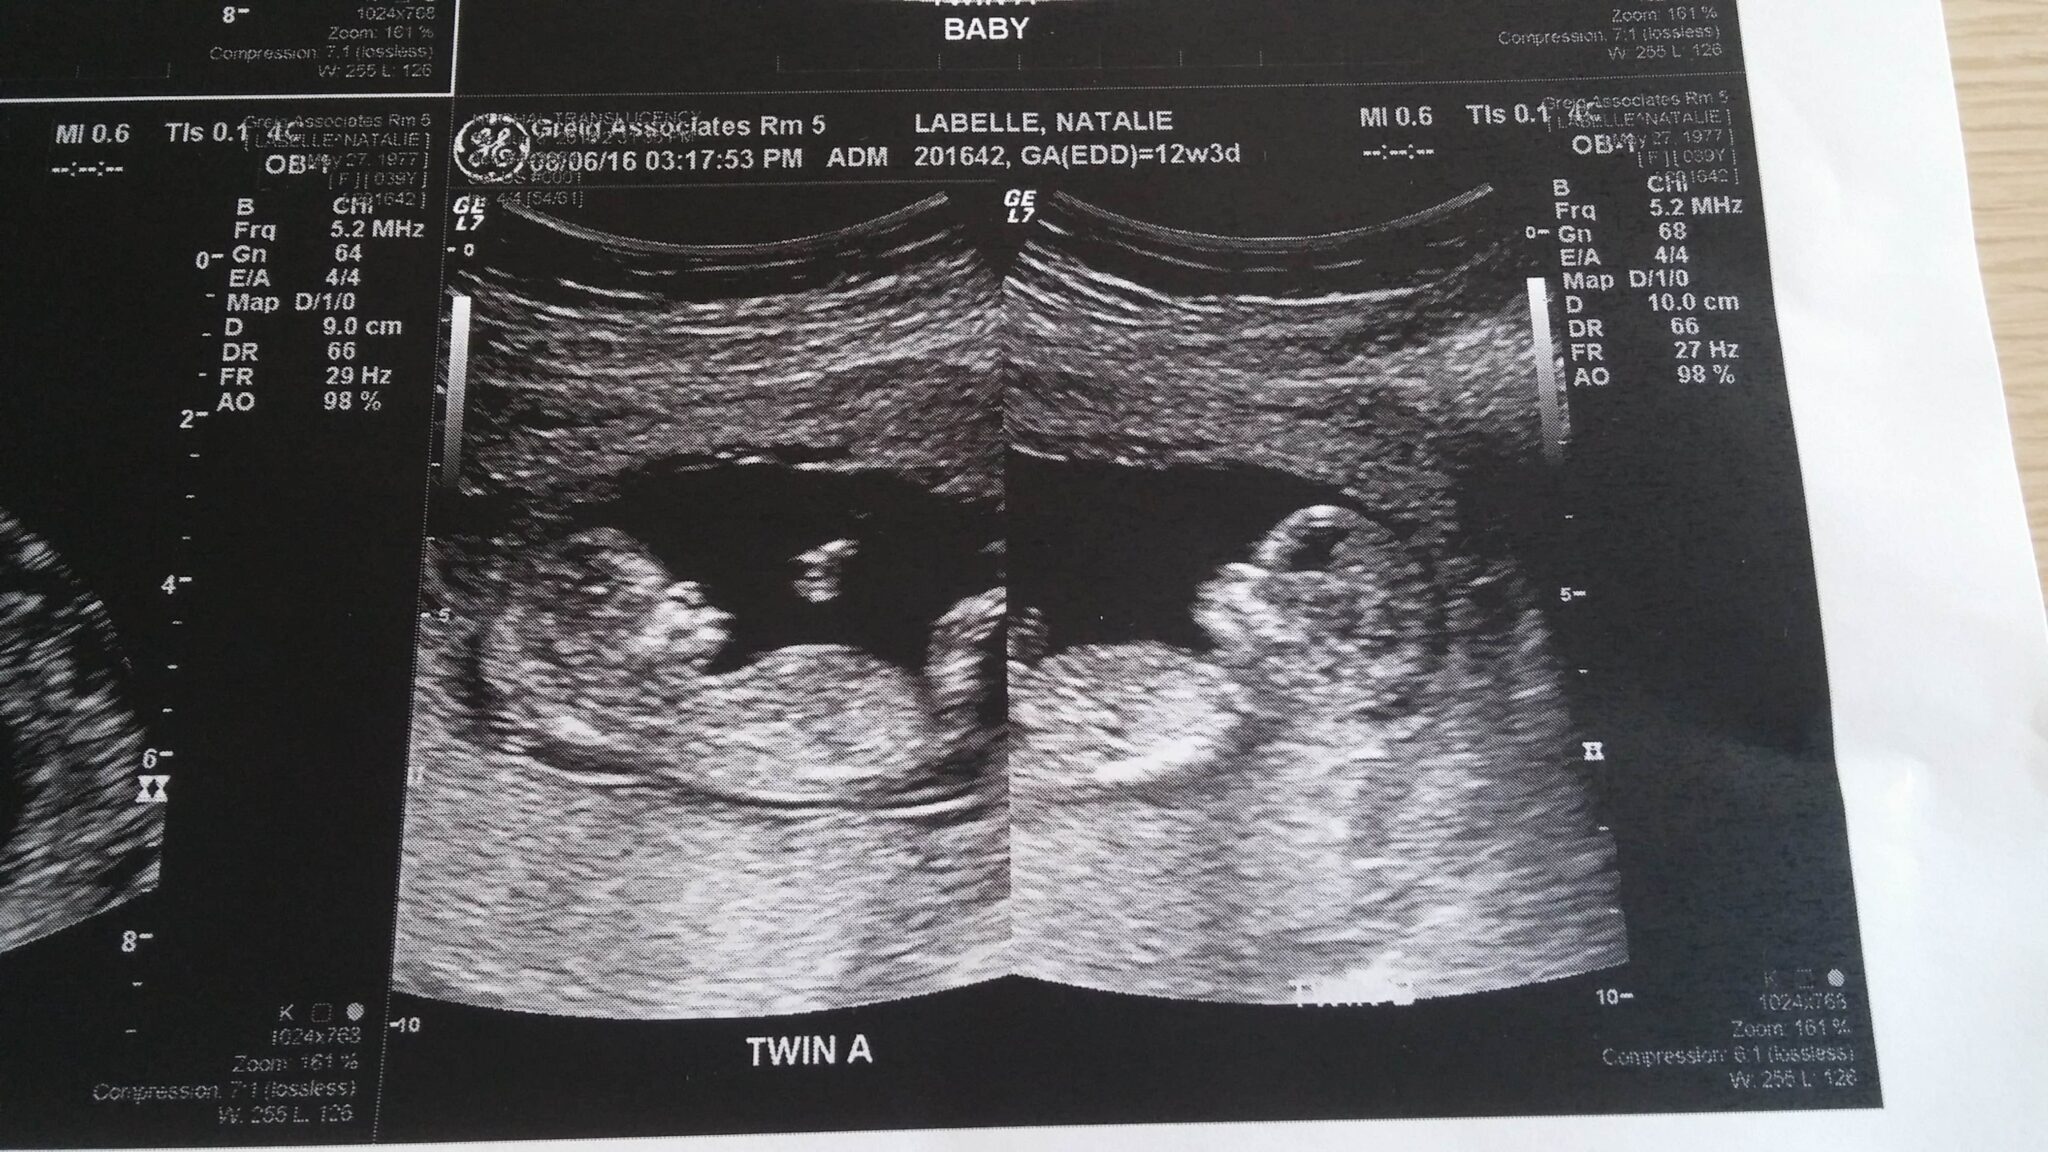

Ultrasound Photos at 12 Weeks Pregnant With Twins